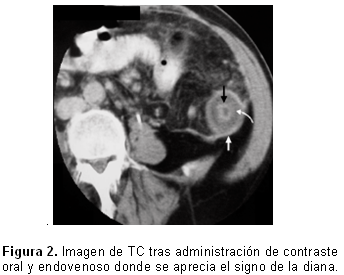

El signo de la diana es observado tanto en la Enfermedad de Crohn como en otras entidades inflamatorias del intestino delgado y representa el aumento de la atenuación postadministración del contraste de las capas interna y externa del asa con conservación de la densidad de la capa media, esta última por presencia de edema. (Figura 2). Habitualmente asociado a engrosamiento parietal, es signo de proceso inflamatorio, aunque puede ser visto en otras entidades como enfermedad isquémica intestinal, enteritis por radiación entre otras. 16, 17